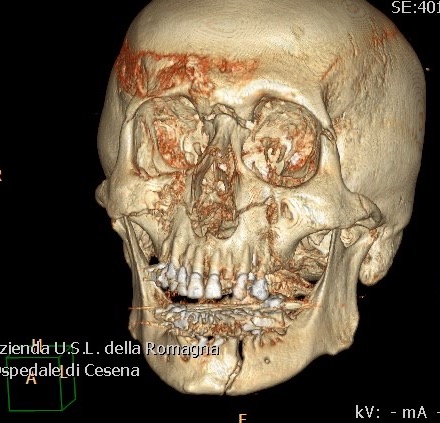

Traumatologia MXF